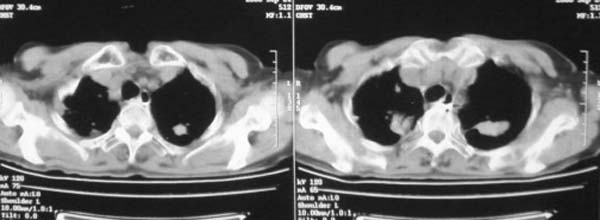

颈部见多枚淋巴结肿大,考虑尘肺继发结核,喉部淋巴结钙化,不除外喉部慢性淋巴结炎、喉淀粉样变及类癌等

肺癌伴纵膈、双颈部淋巴结转移;尘肺。

考虑肺癌伴纵膈、双颈部淋巴结转移;

双上肺结节融合影,周围有纤维条索影,结合粉尘接触史,首先考虑尘肺。双侧颈部有增大淋巴结,有声嘶表现,肺癌淋巴结转移不能排除。可结合颈部淋巴结活检。